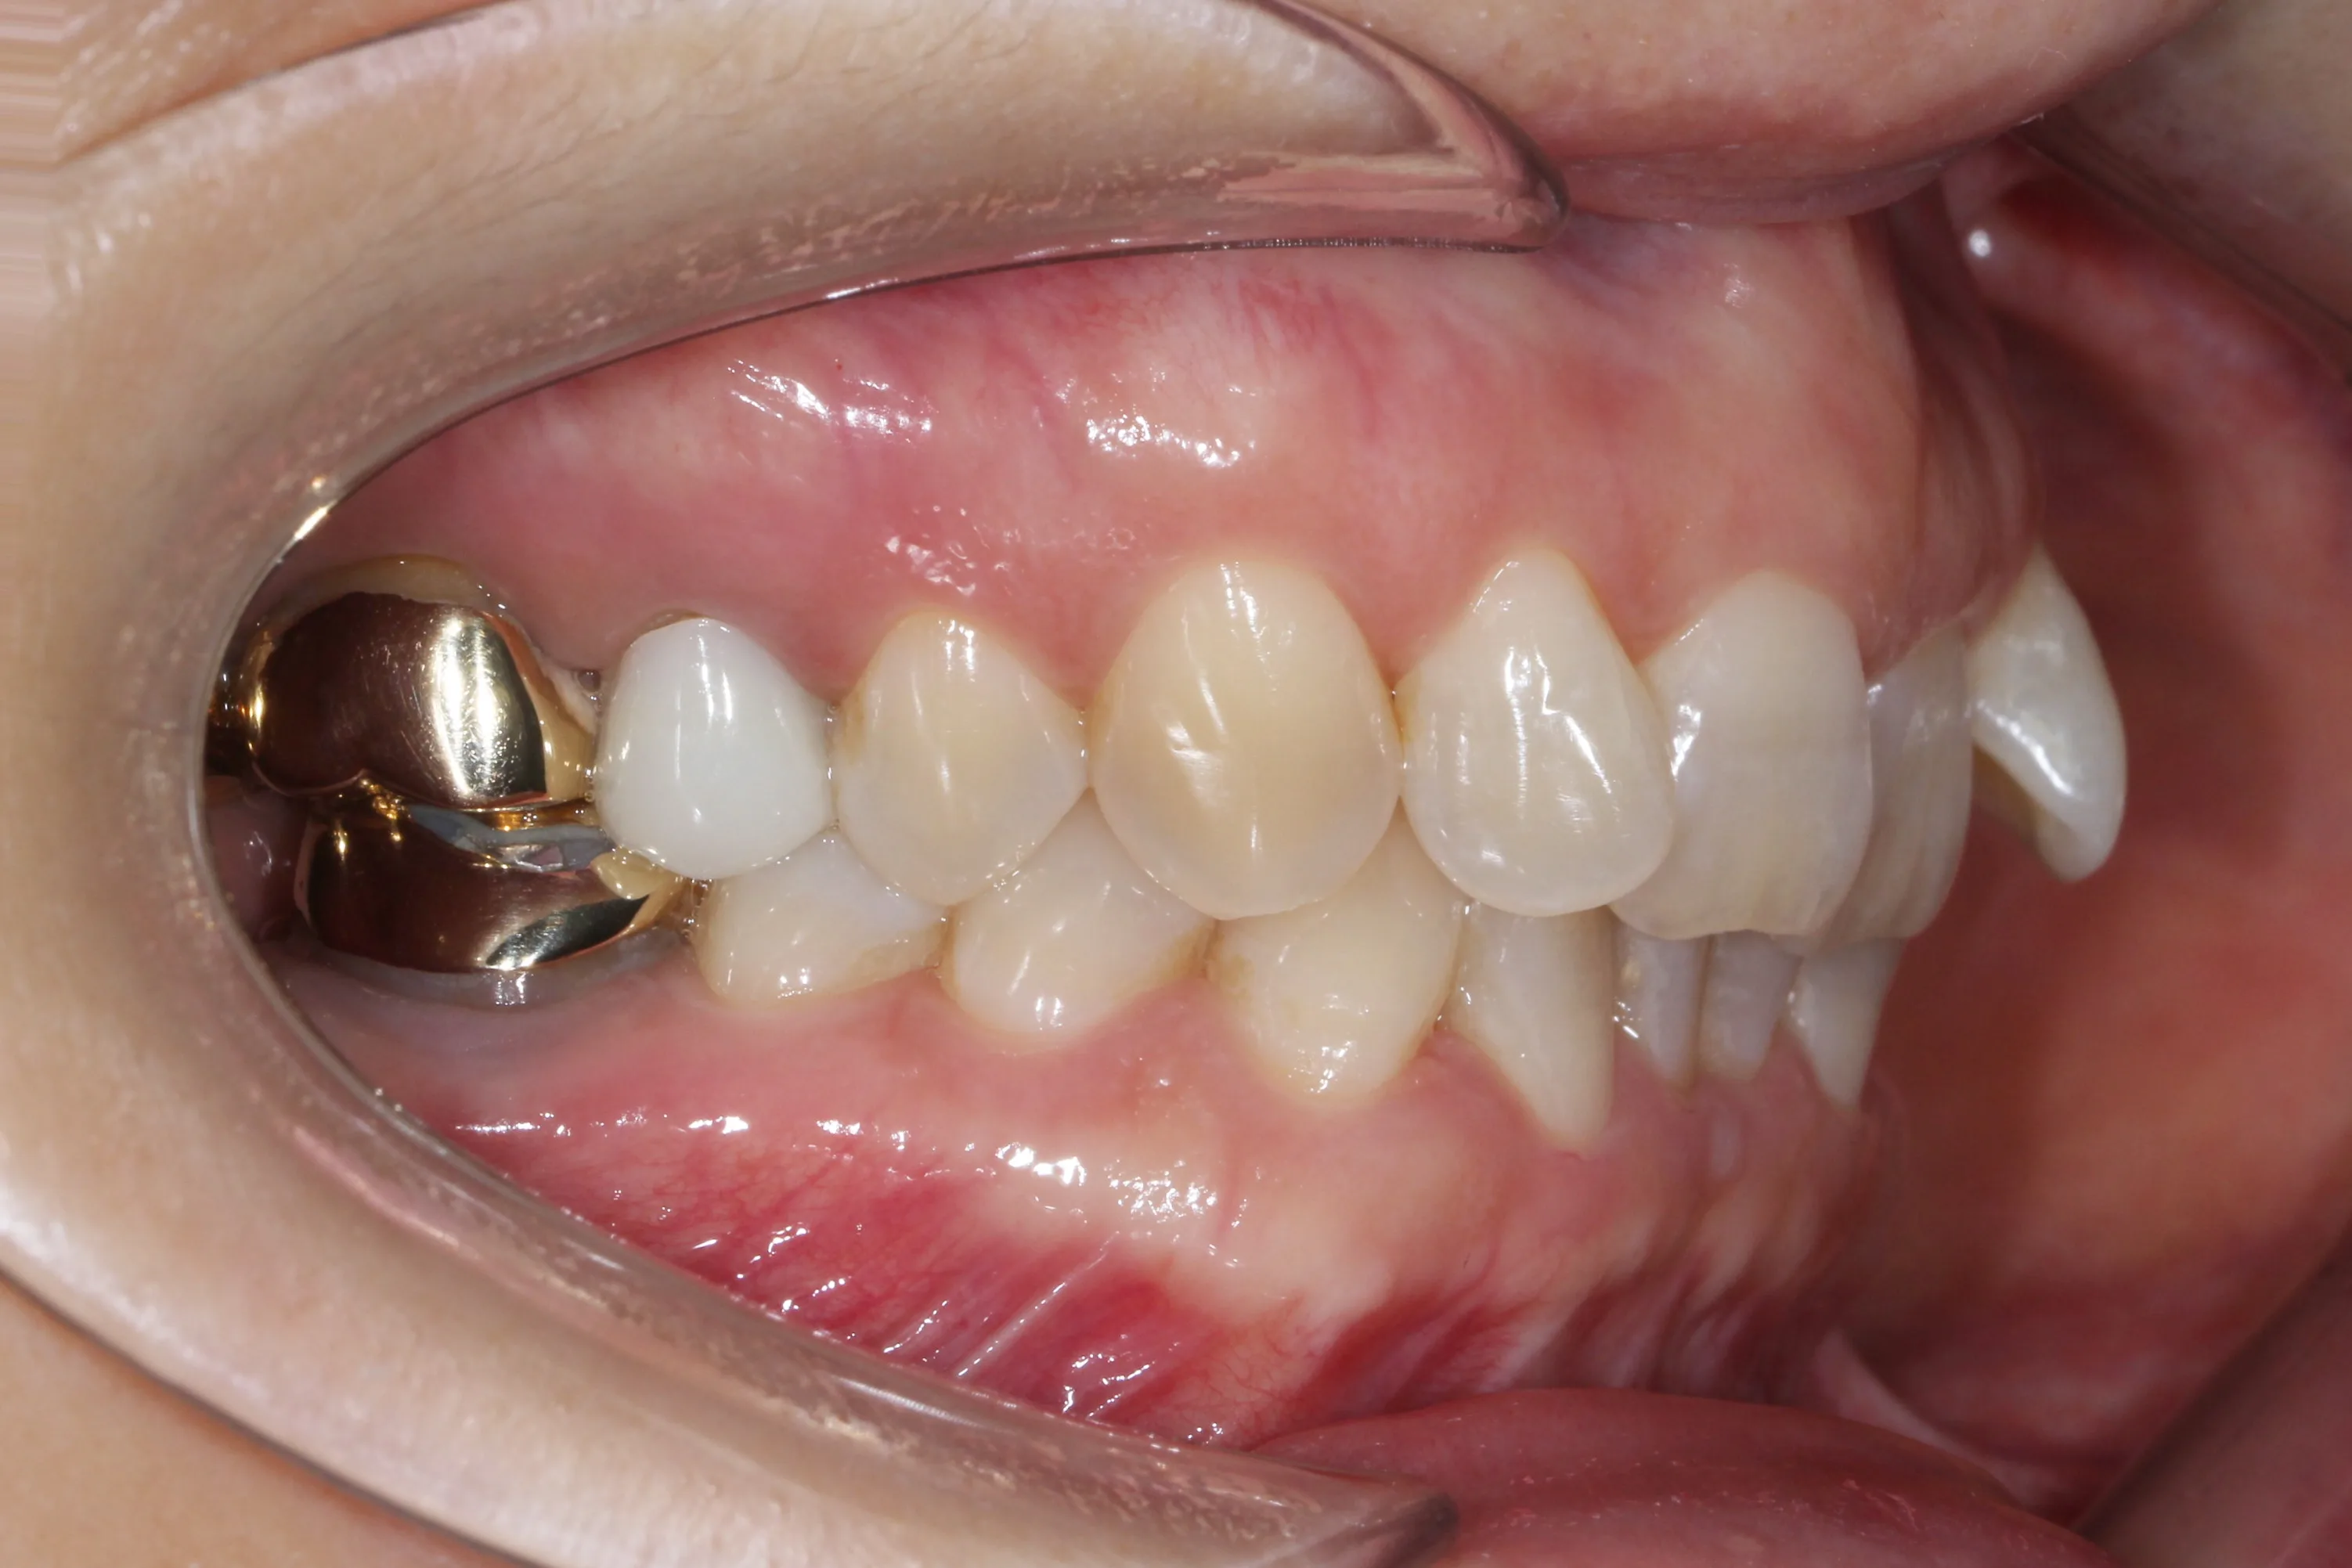

이 환자분은 이미 구강 안에 여러 개의 임플란트와 브릿지 보철물이 있는 상태였습니다. 앞니는 가지런하지 않고, 윗니가 아랫니를 깊게 덮는 과개교합(deepbite)도 있었습니다. 이런 경우 가장 중요한 것은 기존 임플란트와 보철물의 교합을 그대로 유지하면서, 나머지 치아만 가지런하게 배열하는 것입니다.

인비절라인의 디지털 치료 계획을 활용해서, 임플란트와 보철물이 있는 어금니는 움직이지 않도록 고정하고 앞니 위주로만 이동시켰습니다. 덕분에 발치 없이, 고무줄이나 미니스크류 같은 추가 장치 없이도 15개월 만에 치료를 마무리할 수 있었습니다.